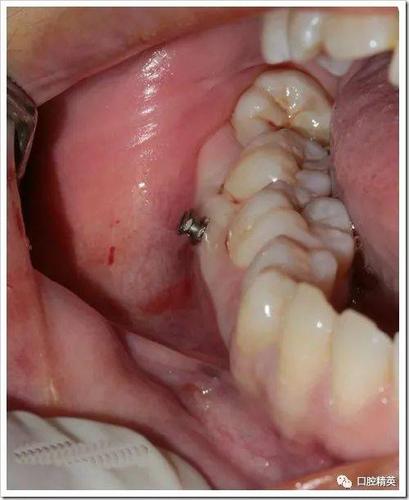

视频的重点环节往往集中在种植钉的植入流程,这部分内容常结合动画演示与实拍画面,清晰呈现每一步操作,术前准备阶段,医生会强调影像学检查(如CBCT)的重要性,以避开牙根、神经血管等解剖结构,确定安全植入位置;同时进行口腔清洁(如洗牙、刮治),确保植入区域无炎症,局部麻醉是关键步骤,视频会展示麻醉药物注射过程,说明麻醉后区域仅感压迫感而无痛感,植入操作中,医生先用微创切口器在牙龈上做小切口(约2-3mm),随后用专用手机备洞(在牙槽骨上制备适合种植钉的窝洞),再将种植旋入窝洞,最后调整露出牙龈部分的高度(约1-2mm,便于后续正畸加力),整个过程通常5-10分钟,创伤小、恢复快。

术后护理与注意事项是视频中的实用内容,直接影响种植钉的成功率,视频会提醒患者24小时内避免刷牙、漱口过激,防止创口出血;术后1周内避免植入侧咀嚼硬物、食用过热或刺激性食物,以免刺激牙龈;日常需加强口腔清洁,使用软毛牙刷、牙线、冲牙器等,避免种植钉周围食物堆积引发炎症,视频会强调异常情况的识别:若出现种植钉松动、脱落,或局部红肿、疼痛加剧、流脓等感染症状,需立即复诊,医生会根据具体情况调整治疗方案(如重新植入或抗感染处理)。